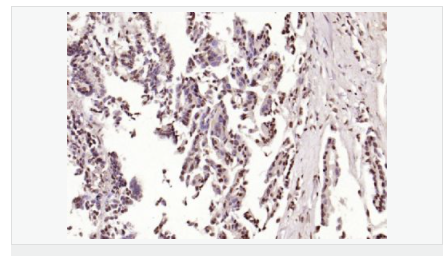

交叉反應:Human,Mouse,Rat(predicted:Dog,Pig,Rabbit,GuineaPig) 推薦應用:IHC-P,IHC-F,ICC,IF,Flow-Cyt,ELISA

| 產(chǎn)品應用 | ELISA=1:5000-10000 IHC-P=1:100-500 IHC-F=1:100-500 Flow-Cyt=1μg/Test ICC=1:100 IF=1:100-500 (石蠟切片需做抗原修復) not yet tested in other applications. optimal dilutions/concentrations should be determined by the end user. |